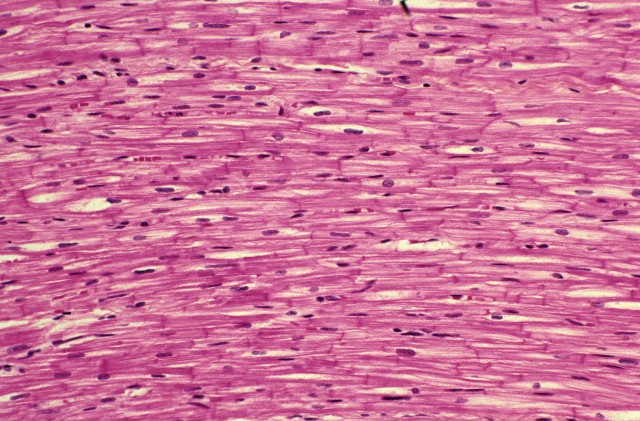

Клетки сердца, соединённые полимерной застёжкой-«липучкой», работают как одно целое.

Клетки сердца, как и многие другие, можно выращивать в лабораторных условиях. Но если мы выращиваем их не просто так, а с целью пересадить больному вместо погибшего кусочка сердечной мышцы, то тут начинаются проблемы. В сердце клетки развиваются в специфическом окружении, их поддерживают и направляют специальные белки, которые помогают им превратиться в сократительное мышечное волокно. Клетки же, выращенные «в пробирке», в лабораторной культуре, лишённые направляющих молекулярных сил, оказываются аморфным и слабыми. Они могут возбуждаться и сокращаться, но они проделывают это несогласованно и разнонаправленно. А нам как раз нужно, чтобы выращенная ткань работала как одно целое, чтобы все клетки, которые её образуют, сокращались вместе и в одном направлении.

Очевидно, чтобы клетки получались такими как надо, нужно смоделировать для них природные, естественные условия развития. Два года назад Милица Радисик (Milica Radisic) и сотрудники её лаборатории в Университете Торонто предложили использовать здесь нить из шёлкового шовного материала, используемого в хирургии для сшивания ран. Шёлк здесь работал как опорная структура, помогающая клеткам вытягиваться в одном направлении, подобно тому, как они формируют мышечное волокно в сердце. Но нить задаёт только одно направление, тогда как живая ткань растёт во все стороны. И в дальнейшем исследователям пришлось усовершенствовать свой метод, создав трёхмерный каркас для выращивания сердечно-мышечной ткани.

В статье в Science Advances авторы описывают, как получить многослойный образец сердечной ткани, который сокращался бы как одно целое. Клетки выращивают на сетке из специального биосовместимого и биодеградируемого полимера; ячеи сетки многоугольные и напоминают пчелиные соты, только они вытянуты в одну сторону. Выросшие на такой сетке, клетки тоже вытягиваются, и, если через них пропустить электрический импульс, они все сокращаются в одном направлении, сгибая полимерный каркас, на котором держатся. На первую сетку накладывается вторая, которая снабжена особыми Т-образными выступами. Эти выступы прочно соединяют оба клеточно-полимерных слоя. Принцип действия здесь такой же, как в застёжке-липучке, две половинки которой соединяются по принципу репейника: микрокрючочки на одной половине цепляются за микропетли на другой половине. После совмещения слоёв они опять же сокращались синхронно и в одном направлении. По словам исследователей, в экспериментах им удавалось так сложить до трёх слоёв, используя разные рисунки сеток.

В идеале новый метод позволит в буквальном смысле штопать сердце после инфарктов: из стволовых клеток пациента выращивается сколь угодно большой фрагмент ткани, по форме и толщине подходящий взамен погибшего участка сердечной мышцы. Сам полимер, на котором растут клетки, не доставит никаких хлопот – через несколько месяцев он рассасывается без следа. Есть и другой плюс: выращивая клетки таким способом, нам не нужно потом прилагать дополнительные усилия, чтобы снять их с субстрата, на котором они росли – иными словами, не нужно подвергать их механическому стрессу, и можно не бояться их повредить. Эту же технологию можно использовать и для выращивания других тканей. Например, уже удалось показать, что кроме кардиомиоцитов, с помощью таких сеток можно выращивать соединительнотканные фибробласты и клетки эндотелия.